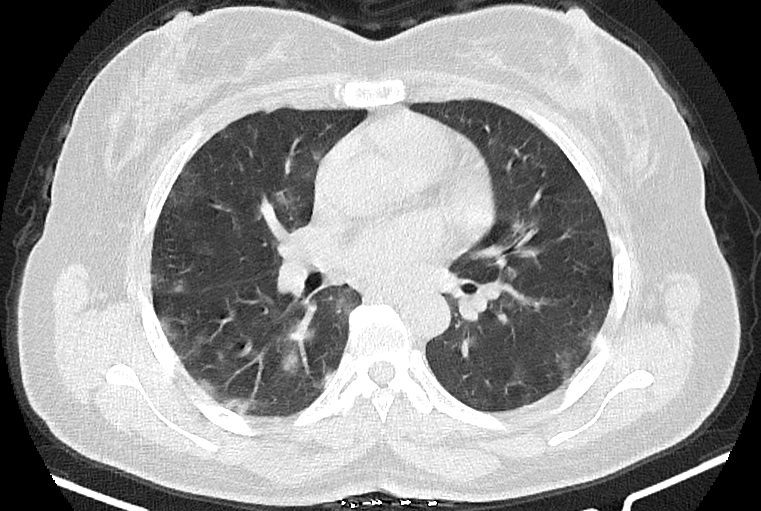

در HRCT از ريه ها(اسپيرال ، مولتي ديتکتور 16، مقاطع اگزيال با ضخامت 1mm بدون فاصله ) ، بدون كنتراست تزريقي :

-Ground glass opacities Patchy پراکنده در ريه ها مشهود است که مطرح کننده Viral pneumonia مي باشد . ( با درگيري 20 درصد حجم ريه )

-کلسیفیکاسیون دیواره آئورت و عروق کرونر ، تغییرات DJD در ستون فقرات ونشانه های CABG مشهود است .

نتیجه : Highly suggestive of COVID-19